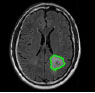

Brain tumors perpetuate because of the unusual advancement of cells that multiply uncontrollably [1]. Tumors begin from brain cells around the membrane of the brain (meninges), organs, or nerves. The primary subtypes of brain tumors are benign and malignant (Fig. 1). Benign tumors develop slowly and are non-cancerous and less invasive. On the contrary, a malignant tumor is a harmful tumor, expanding rapidly with unknown borders that invade other strong body cells. It is recognized as a primary malignant tumor found in the brain. It is a second malignant tumor [2] if it originates somewhere in the body and extends to the brain. Computed Tomography, Single-Photon Emission Computed Tomography, Positron Emission Tomography (PET), Magnetic Resonance Spectroscopy, and Magnetic Resonance Imaging (MRI) are all clinical imaging modalities that are used to impart critical information regarding the form, scale, area, and metabolism of brain tumors. These modalities are used to provide the most up-to-date information on brain tumors. Due to its remarkable delicate tissue distinction and extensive accessibility, magnetic resonance scanning is the dominant methodology [3].

2.2. Segmentation

The next move is to segment the brain tumor MR image after enhancing the brain MR image. Segmentation is used to distinguish the foreground and background of an image. Segmenting an image often reduces the time it takes to process subsequent operations on the image. Although human eyes can quickly identify and isolate objects of interest from background tissues, algorithm formulation is a challenging task. Since the subsequent steps are dependent on the segmented area, segmentation directs the outcome of the entire study. Segmentation algorithms use region expansion, deformable models, histogram equalization, and image identification strategies like fuzzy clustering and neural networks to modulate the strength or texture of pictures. Region-based and edge fragmentation, dynamic and global thresholding, gradient drivers, watershed fragmentation, hybrid segmentation, and volumetric fragmentation, supervised and unsupervised segmentation are all readily accessible. Segmentation is achieved by identifying all voxels or pixels that belong to the object or those that form boundaries. The former employs pixel intensity, whereas the latter employs picture gradients with high values at the edges. Because it requires pixel classification, segmentation is sometimes viewed as a pattern recognition task.

Fragmentation is the procedure of breaking down an image into several segments to detect the tumor region. In this paper, different segmentation approaches based on grey level, model-based, feature texture-based, and hybrid segmentation (Fig. 5) are discussed, and these segmentation methods are summarized toward the end of this section.

Now, based on the discussed segmentation algorithms, which are used by various researchers [56, 57, 62-64] in their work for tumor diagnosis, an analysis is done in Table 2 for better visualization of the readers, where the second column depicts the data sets used followed by their choice of segmentation algorithm and then input MRI imagery taken, then segmented and detected resultant images. Also, in Table 3, various pros and cons are discussed amongst the existing segmentation algorithms.